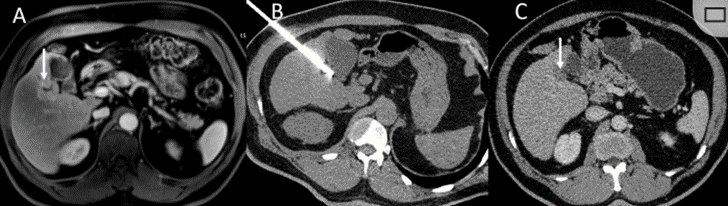

冷凍消融膽囊附近腫瘤病灶

(A)動脈期 MRI 顯示膽囊附近有外周增強病變(箭頭)。

(B)手術過程中 CT 顯示冷凍探針位于病灶內。

(C)消融后,術后 1 個月CT 顯示完全消融(箭頭)。